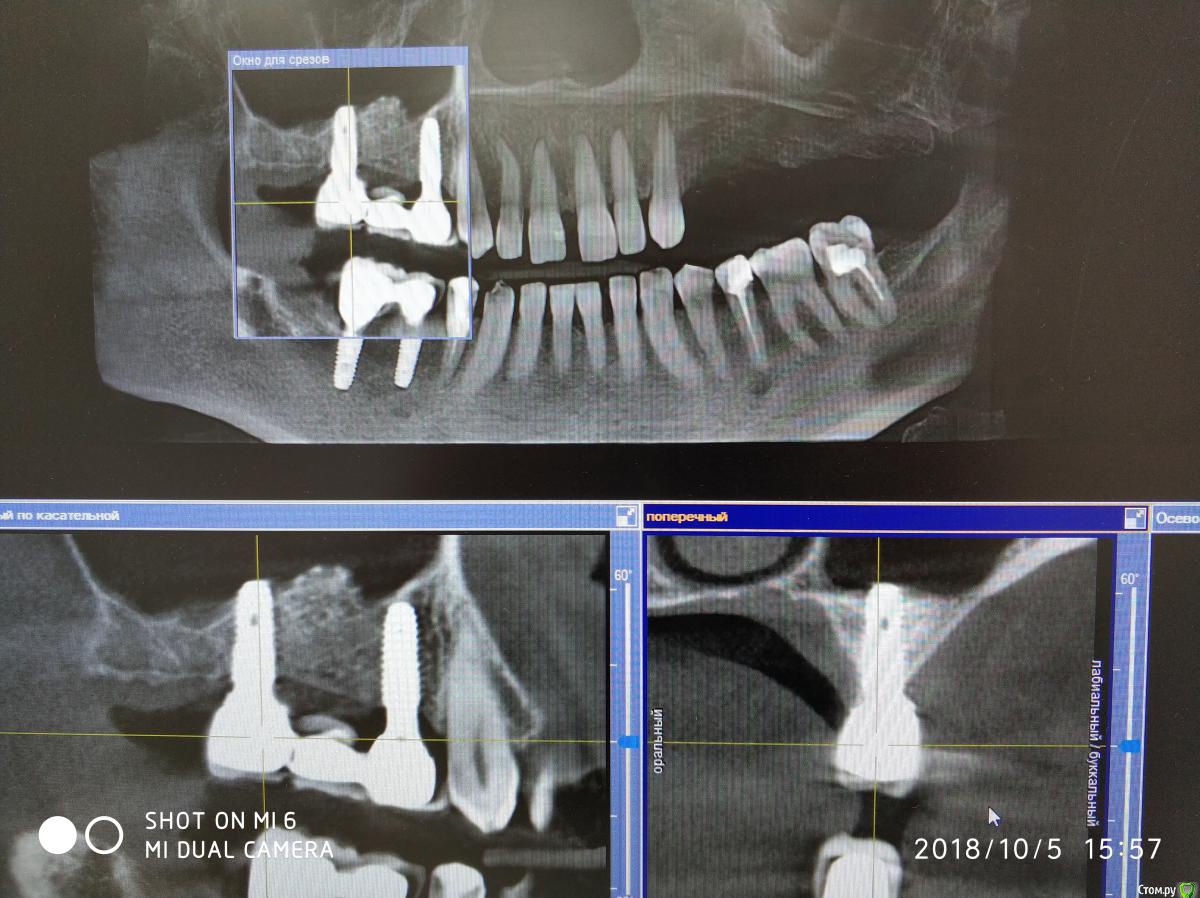

Nazim_NV86 Опубликовано 7 августа, 2018 Автор Поделиться Опубликовано 7 августа, 2018 14-16 с синусом стоят год, стоит металлокерамика. 45,46 пока с фдм. Осстем. Ссылка на комментарий

Nazim_NV86 Опубликовано 11 октября, 2018 Автор Поделиться Опубликовано 11 октября, 2018 Появилась свежая КЛКТ Ссылка на комментарий

red_butler Опубликовано 11 октября, 2018 Поделиться Опубликовано 11 октября, 2018 Как сделает - выложу скрины. покажите срезы синусов, что нам толку от имплантов Ссылка на комментарий

Nazim_NV86 Опубликовано 12 октября, 2018 Автор Поделиться Опубликовано 12 октября, 2018 Срезы пазух. На чувствительность языка жалоб не слышал. Как приедет тесты сделаю. Ссылка на комментарий